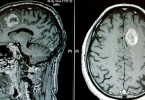

3.定期复查:术后定期复查是至关重要的,可以及时发现并处理任何并发症或复发的情况。根据医生的建议,可能需要进行内窥镜检查、影像学检查或其他必要的评估。